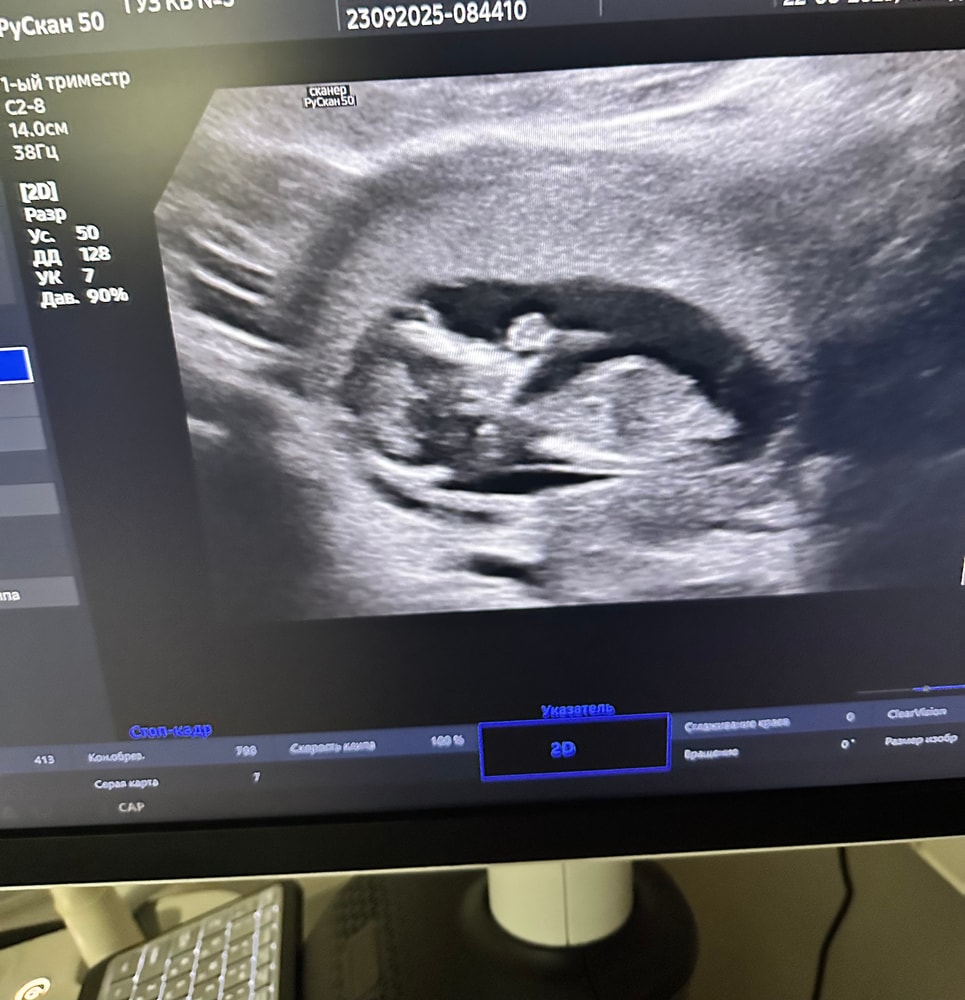

Прошли первый скрининг, всё, слава богу, хорошо.🥹

В пределах нормы. Носик хорошенький. Пороков не обнаружено …теперь остаётся только ждать кровь, держу кулачки чтобы там тоже всё было хорошо 🙏🏻💕

такая маленькая…вертелась крутилась, пальчик сосала 🥰🤭

Единственное по М срок 13 и 2, а по УЗИ поставили 12 и 6…но ничего не сказали, надеюсь это нормально 🙂

Оставлю фото на память 📌💝🐣